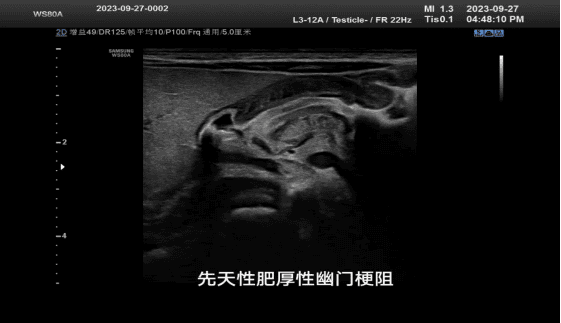

可清晰显示胃肠壁层次结构、厚度,能判断病变所侵犯层次及累及范围,还可以动态观察病变的实时变化,图像层次清晰,细节分辨能力高,有助于患儿消化道疾病(如先天性肥厚性幽门梗阻、阑尾炎、腹型紫癜、炎性肠病等)的临床快速诊断,更快速有效地进行下一步诊治,减少患儿的就诊及住院时间。